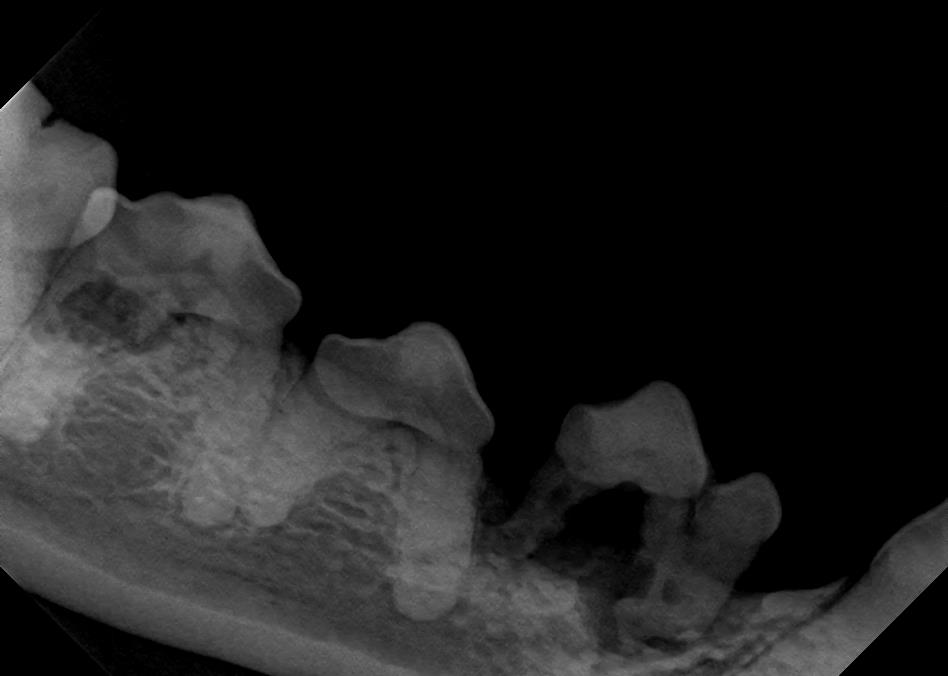

Examples of healthy teeth:

At A Couple of Vets, our animal hospital staff is well-versed in the latest dental cleaning techniques to remove plaque and tarter from the teeth’s surface as well as from below the gum line. We perform dental x-rays at every cleaning to ensure that the teeth are completely healthy. They may look good on the surface, but many problems occur below the gum line and are only visible with x-rays.